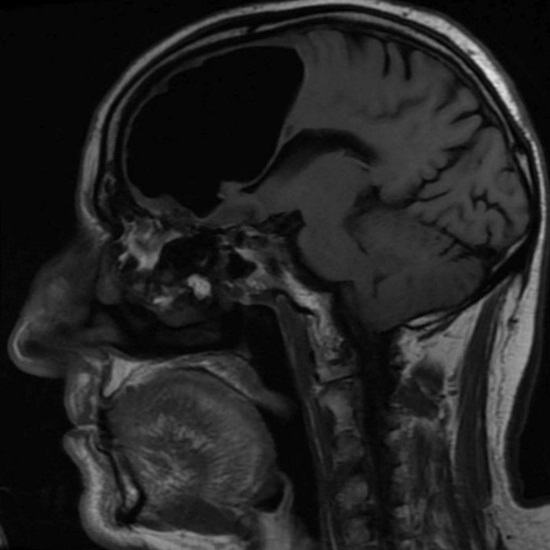

Pohjois-Irlannin lääkärit hämmästyivät tutkiessaan äskettäin 84-vuotias potilas, joka tuli heidän luokseen pahoinvoinnilla. Tehtyään miehen pään magneettikuvauskuvauksen lääkärit huomasi yllättäen, että hän puuttui osasta oikeaa etuosaa aivojen lohko. Sen sijaan eläkeläisen kallo oli ilmaa taskussa. Sitten lääkärit päättivät, että todellinen aivojen fragmentti potilas ei hävinnyt mihinkään, mutta häntä sekoitettiin tämän epänormaalin suuntaan onkalo.

Sairaalan henkilökunta ehdotti potilaan käyttäytymistä vaikeana toimenpide ilmataskun poistamiseksi, mutta mies kieltäytyi leikkauksesta. Eläkeläisen mukaan hänen ikä, hän yleensä tuntuu erittäin hyvältä eikä aikoo asettaa henkensä vaaraan makaamalla skalpelin alla. K onneksi pian irlantilaisten hyvinvointi katosi ja nykyhetkessä tällä hetkellä hänellä ei ole mitään epämukavuutta, joka liittyy heidän epänormaali terveydentila.